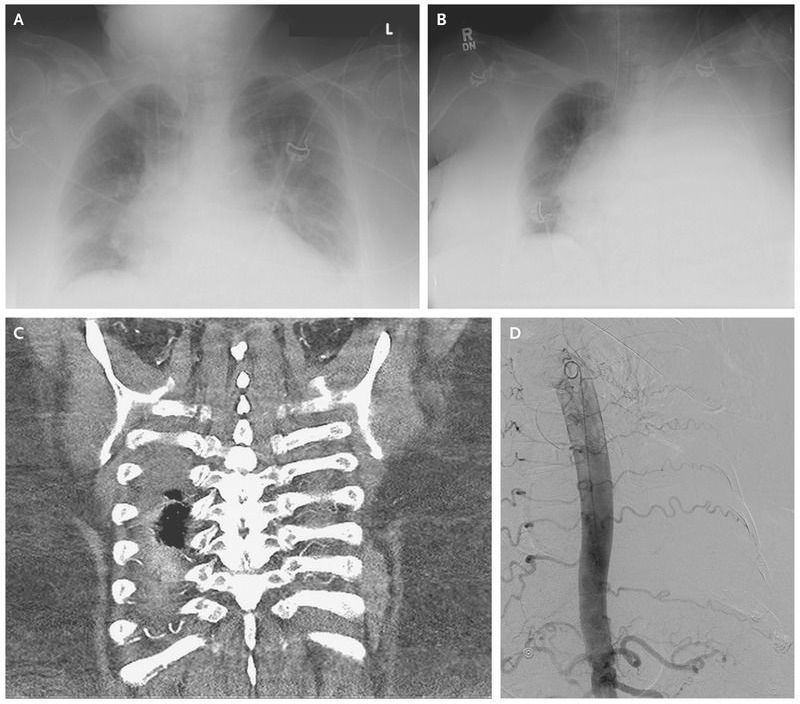

A 65-year-old woman with atherosclerotic cardiovascular disease and renal failure was hospitalized for acute respiratory failure and bilateral pleural effusions associated with pneumonia (Panel A). To rule out the presence of empyema, a diagnostic, ultrasonography-guided thoracentesis was performed in the left lung in the 9th and 10th intercostal spaces. The initial fluid that was extracted had a brown discoloration but was transudative and was thought to be associated with the patient’s cardiorenal disease. Unfortunately, hemothorax developed shortly after the procedure (Panel B). Computed tomography and angiography of the chest revealed tortuous intercostal arteries, which had potentially contributed to iatrogenic arterial injury (Panel C). The hemothorax was managed successfully with chest-tube insertion and angiographic coil embolization (Panel D), and the patient’s clinical condition improved. There have been reported correlations between increased tortuosity of intercostal arteries and decreased safe space for thoracentesis, particularly in older patients.